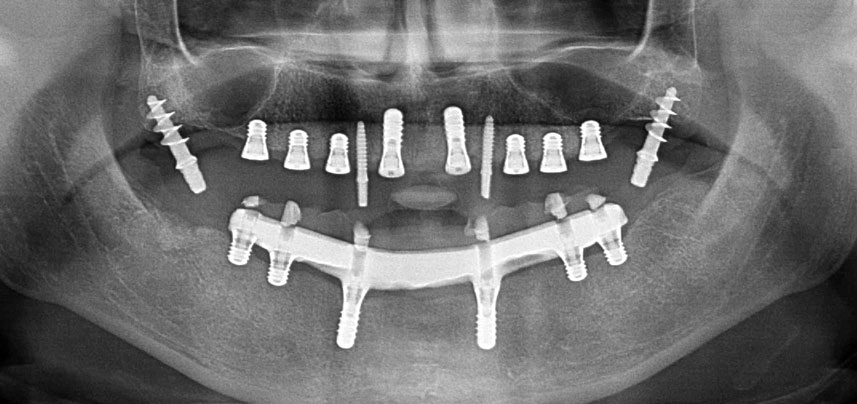

Postoperative Panoramaschichtaufnahme

Abb. 10: Die postoperative Panoramaschichtaufnahme zeigt alle Implantate an den richtigen Positionen, einschließlich der temporären Implantate in der Pterygoid-Region.